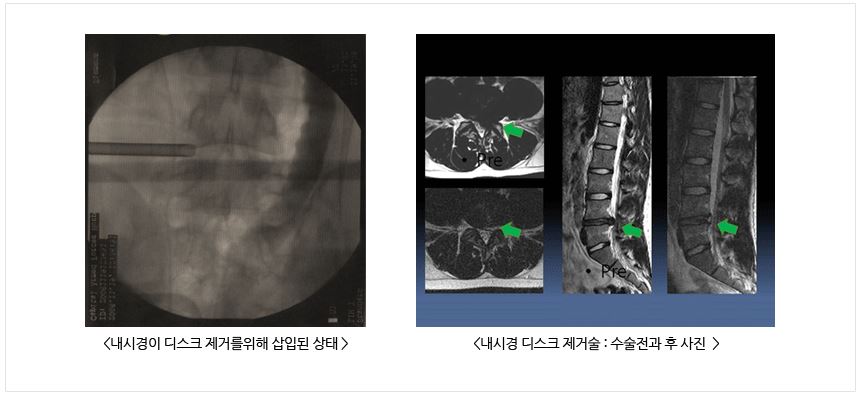

내시경 디스크 제거술 : 고식적인 디스크 제거술에 비하여 수술 절개 범위가 적고 수술 후 회복이 빠릅니다. 하지만, 허리 디스크 중 내시경 디스크 제거술로 치료가 가능한 경우는 일부이기 때문에 전문의와 상담이 필요합니다.